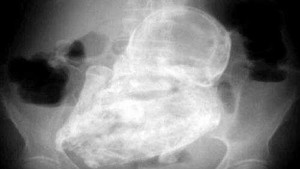

(VTC News) - Bệnh viện Đa khoa tỉnh Khánh Hòa đã phối hợp với Bệnh viện Đa khoa khu vực Cam Ranh tổ chức cuộc hội chẩn để tìm ra hướng xử lý đối với thai đá.